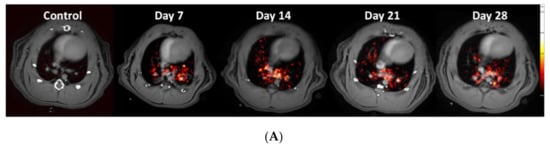

Uptake of the novel PET-tracer CBP-Cu64 in lung tissue was assessed at day 7, 14, 21, and 28 post-bleomycin or saline (as control) i.t. administration. Representative PET images of the CBP-Cu64 show uptake in the lungs at all measured time points post-challenge (Figure 4A). There was a higher total uptake of the tracer in the lungs of bleomycin-exposed animals compared to controls (Figure 4B). Large variation of the uptake within the bleomycin group was observed, especially at later time points. From a detailed visual inspection, it was evident that the major PET signal did not overlap directly with the MRI-identified lesions. Specifically, the PET tracer uptake was often localized at the border of the lesions identified by MRI. The PET signal evaluation from the various compartments (lesion regions vs. surrounding healthy appearing tissue), indicated a slowly increasing area of active fibrosis (Figure 4C,D). This observation was further confirmed in terms of tracer uptake in the tissue on a microscopic level by autoradiography, showing mainly tracer uptake occurring in dense areas (i.e., identified as tissue signal by MRI) but also in non-fibrotic areas close to fibrotic foci, as confirmed by H&E stained sections (Figure 4E).

Figure 4.

Longitudinal PET imaging in Group I, during 28 days of bleomycin-induced lung injury, using the novel PET tracer for assessment of non-cross-linked Collagen-I. (A) Representative PET images of lungs from rats challenged by i.t. administration of bleomycin (or saline as controls) on day 7, 14, 21, and 28 post-challenge. (B) Quantification of the total lung tissue signal uptake expressed as fraction uptake (total lung uptake of the injected dose [%ID]). The PET signal was assessed in different compartments, defined as high signal regions based on the TESHORT and TELONG, sequences from obtained MRI scans. (C) PET signal uptake from TELONG defined lesions (yellow area) and surrounding area within the total Lung-ROI. (D) PET signal uptake within the TESHORT defined lesions (blue) and surrounding area within the total Lung-ROI. (E) Autoradiography was performed in few of the animals to assess microscopic tracer uptake directly after the PET scan. One time point (day 21) from the bleomycin-challenged group is presented here. Lungs R1–R4 are Right lung lobes from the top section and downwards. Left referring to the left lung lobe. Enhanced signal uptake of CBP-Cu64 is indicated by arrows (in the case of long streaks of signal) or encircled (in the case of focused area), where also fibrotic tissue is observed in close proximity to healthy tissue and vessel-airway presence.